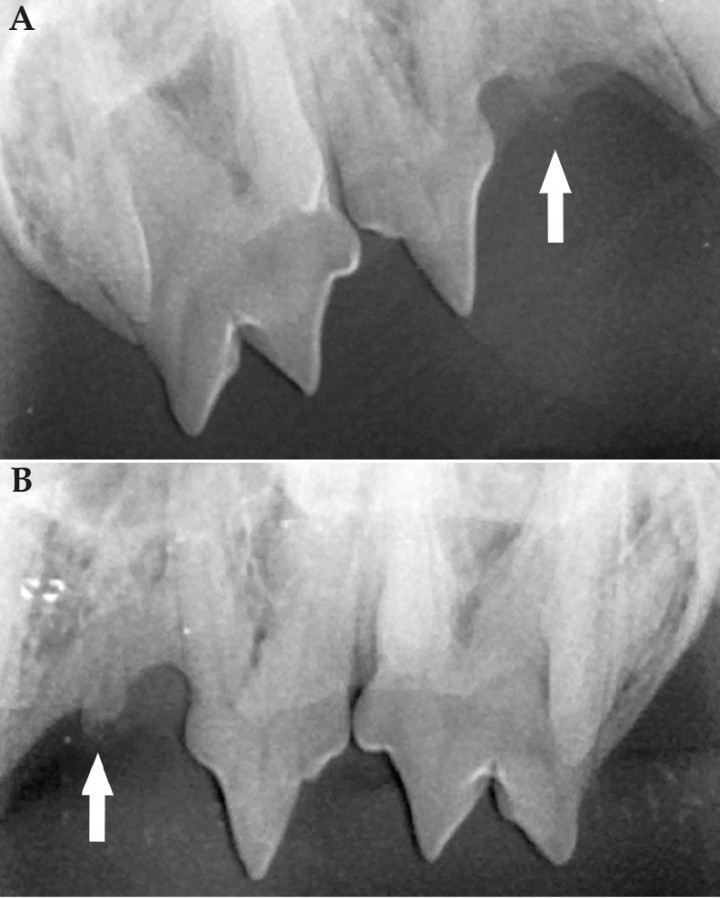

<p>(<strong>A</strong>) Radiografía dental extraoral de la arcada maxilar derecha. Se observa alteración radiológica compatible con RD de tipo 2 del 106 (flecha). (<strong>B</strong>) Radiografía dental extraoral de la arcada maxilar izquierda. Se observa alteración radiológica compatible con RD de tipo 2 del 206 (flecha).</p>

(A) Radiografía dental extraoral de la arcada maxilar derecha. Se observa alteración radiológica compatible con RD de tipo 2 del 106 (flecha). (B) Radiografía dental extraoral de la arcada maxilar izquierda. Se observa alteración radiológica compatible con RD de tipo 2 del 206 (flecha).